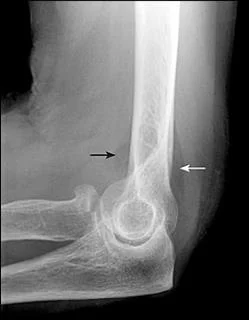

X-ray

- A visible posterior fat pad on the lateral view of the elbow is a sign of occult intra-articular trauma